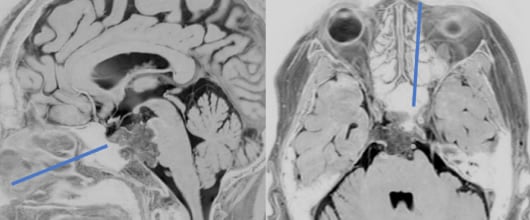

頭蓋底腫瘍とは

血管や神経がひしめく複雑な部位にできるのが頭蓋底腫瘍です。細い血管が1本ダメージを受けただけで、手足・顔面の麻痺などが起きてしまうこともあります。頭蓋底手術においては、いかに症状を抑えながら問題となっている腫瘍に対処するのか、が最も重要です。知識や経験はもちろんのこと、北大病院では運動神経や視力、聴力、顔面神経等の脳機能を守るために高度なモニタリングを駆使して手術を行います。腫瘍によっては、頭を切らずに、鼻の穴から高精細の内視鏡を挿入し、脳へのダメージを最小限に抑えた頭蓋底手術も可能な場合があります。また、手術だけではなく、最適な治療を組み合わせて提供できるように放射線治療科などの他の専門科と連携して治療に取り組んでいます。